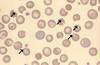

A

Howell-Jolly Bodies

* nuclear remnant inside RBC

* sign of regeneration

* if no reticulocytes seen, consider macrophage dysfunction (splenic)